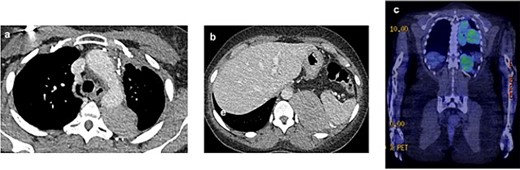

In July 2021, a 18F-fluorodeoxyglucose positron emission tomography integrated with computed tomography revealed active disease in the left hemithorax, with bulky costophrenic and retrocrural disease invading the left aspect of the body and ipsilateral pedicle of the 12th thoracic vertebra, with a maximum standardized uptake value (SUVmax) of 5.9 (Fig. 1).

2021 PET and CT scan showing recurrence extension, involving the left parietal pleura (a, c) and the retroperitoneal tissue with spleen capsule (b).